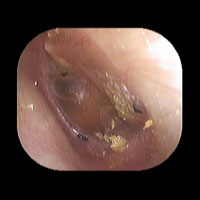

右急性中耳炎(中等症)

鼓膜がやや赤くなっています。鼓膜の奥に膿が透けて見えています。鼓膜の腫れはありません。抗生剤の内服で鼓膜切開を行わずに16日目で治りました。

16日目